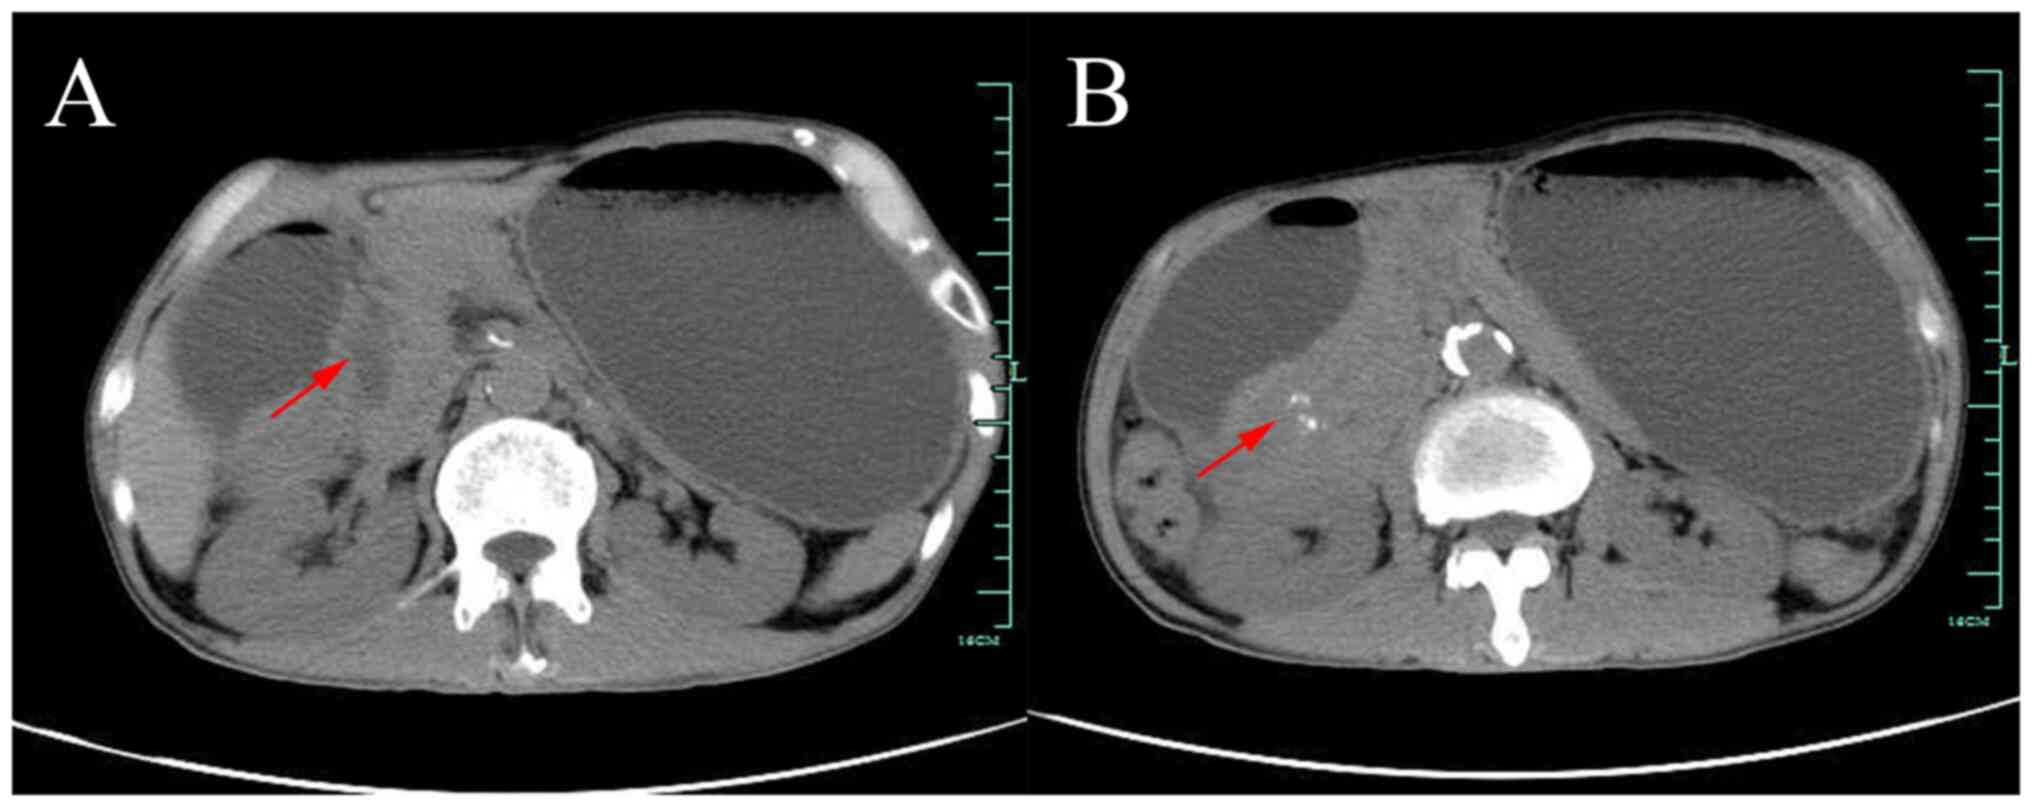

Following admission, laboratory tests revealed carcinoembryonic antigen (CEA) level of 5.49 ng/ml, and ferritin level of 645.1 ng/ml, with a normal carbohydrate antigen 19-9 (CA 19-9) level. The rest of the patient's liver function, troponin, thyroid function, parathyroid hormone, coagulation function, HIV, hepatitis B, hepatitis C, autoantibodies, immunoglobulin, blood and urine light chain were all normal. Abdominal computed tomography (CT) suggested thickening of the sinusoidal wall with gastric retention, patchy shadow of the pancreatic-gastric gap with calcification, mild dilatation of the intra- and extrahepatic bile ducts and dilated pancreatic ducts (Fig. 1). At this point, it became clear that the patient was not simply suffering from gastroenteritis but rather from gastric retention, so the patient was transferred to the gastroenterology department. The patient was treated with fasting, gastrointestinal decompression, acid suppression and rehydration support. After treatment, the patient's urine output increased, creatinine level returned to normal, blood calcium level returned to normal and hyponatremia was more persistent at 127 mmol/l.

Figure 1

CT images. CT revealed significant gastric dilatation and pancreatic compression distortion. (A) An ill-defined hypodense lesion was visible between the pancreas and gastroduodenum, with (B) speckled calcification and poor demarcation from the duodenal wall (red arrows). CT, computed tomography.